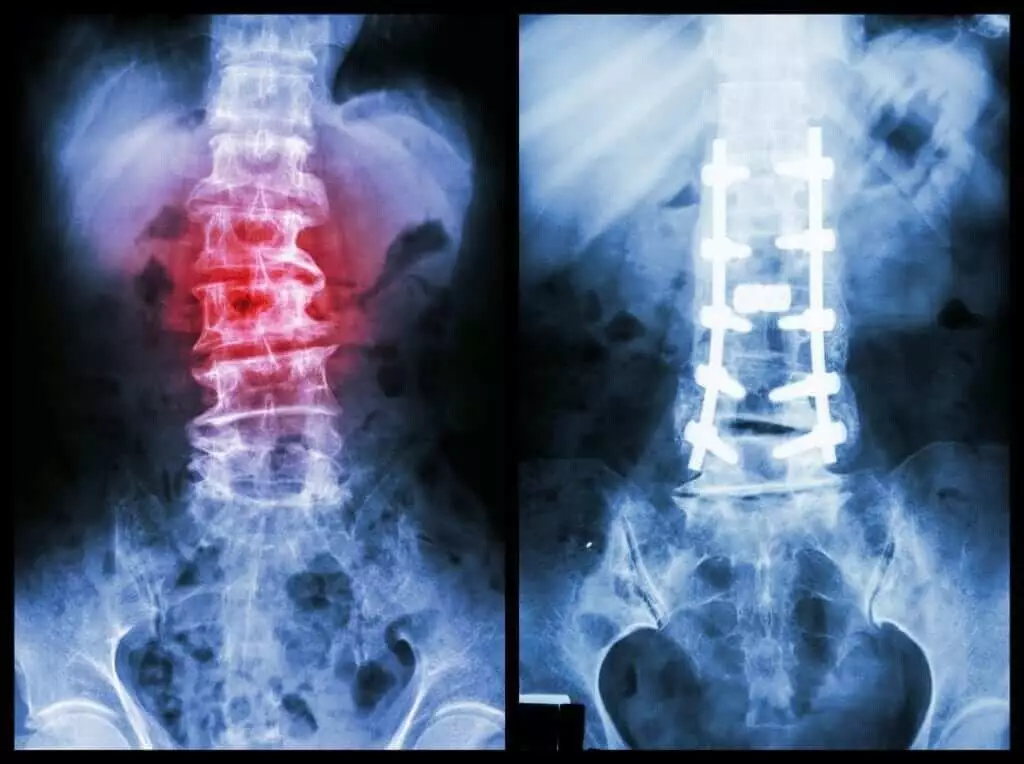

در صورتی که متخصص تشخیص دهد روشهای محافظهکارانه کافی نیست یا ستون فقرات ناپایدار شده است، عمل جراحی توصیه میشود. جراحیهای رایج شامل:

اگر ستون فقرات به شدت ناپایدار شده و خطر فشار بر نخاع وجود داشته باشد، ممکن است فیوژن مهرهها (جوش دادن مهرهها به کمک پیچ و پلاک یا گرافت استخوانی) نیز ضرورت پیدا کند.